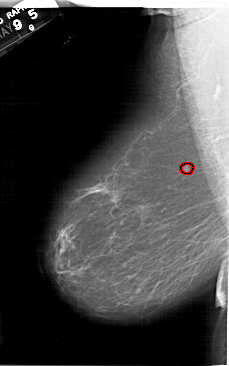

A_1164_1.LEFT_CC

LEFT_CC LINES 6496 PIXELS_PER_LINE 4141 BITS_PER_PIXEL 12 RESOLUTION 43.5 OVERLAY

FILE: A_1164_1.LEFT_CC.OVERLAY

TOTAL_ABNORMALITIES 1

ABNORMALITY 1

LESION_TYPE MASS SHAPE IRREGULAR MARGINS ILL_DEFINED

ASSESSMENT 4

SUBTLETY 4

PATHOLOGY MALIGNANT

TOTAL_OUTLINES 1

BOUNDARY